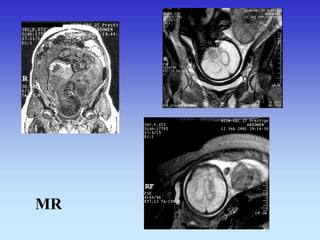

NEURORADIOLOŠKA OBRADA ZAPOČINJE VEĆ INTRAUTERINO

UZV

MR